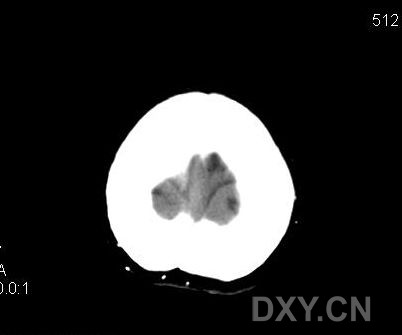

标题: CT11931:请看看有无异常!!

女性,62岁.头顶部不适,自述"头顶发凉"多年.

脑内未见异常,顶部头皮下怎么有多个点状高密度影?重建个骨窗吧!

头皮下多个点状高密度影,ct值220hu左右,考虑是什么东西

头顶部皮下软组织内多个点状高密度影,ct值220hu左右,考虑是什么东西???

颅内ct平扫未间异常。顶部皮下可见多发小点状钙化影,病人无个伤排除异物情况下,考虑囊虫病后遗改变,建议上传软组织窗。

颅顶部皮下多发小结节状高密度影,边缘锐利;颅内未见异常,结合有头顶发凉病史,考虑多发静脉石可能。

患者没有明显外伤史,对于囊虫病,我觉的为什么只局限在头顶部皮下,而颅内一切正常。我比较倾向于静脉石可能。